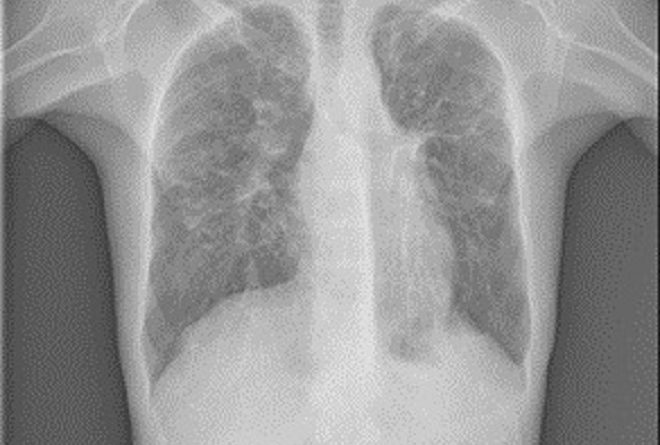

Simptomele pacienţilor cu mucoviscidoză variază în funcţie de vârstă, tabloul clinic al afecţiunii fiind compus din: Retard de creştere la copil, icter prelungit cu caracter obstructiv, ileus meconial (obstrucţia intestinului subţire la nou născut), edeme hipoproteice, transpiraţie sărată (hainuţele nou născutului sunt impregnate cu sare), şi wheezing (respiraţie şuierătoare) la nou născuţi şi sugari; Polipi la copii, durere şi senzaţie de presiune la nivelul sinusurilor faciale, cefalee, dureri abdominale cronice, deshidratare severă cu pierdere excesivă de sare prin transpiraţie, senzaţie de greaţă şi vărsături, scaune moi, deschise la culoare, după consumul de alimente bogate în grăsimi, ascită (acumulare de lichid intraabdominal) hemoroizi, prolaps rectal, întârzierea pubertăţii şi infertilitate (în cazul adolescenţilor de sex masculin); Simptome respiratorii: tuse cronică cu expectoraţie mucopurulentă, foarte rar tuse seacă, dispnee, wheezing, cianoză, infecţii respiratorii frecvente (în special cu Pseudomonas aeruginosa, Stafilococul auriu sau Escherichia Colli, insuficienţă respiratorie cu hipoxie (scăderea cantităţii de oxigen din corp), scăderea toleranţei la efort.

Substituirea enzimatică a deficitului pancreatic pentru creşterea absorbţiei grăsimilor alimentare la nivel digestiv; Complicaţii la nivelul aparatului respirator: bronşiectazii colonizate cu Pseudomonas Aeruginosa, Staphylococcus Aureus sau Escherichia Coli, hemoptizie (tuse cu sânge), pneumotorax, insuficienţă respiratorie, polipoză nazală şi exacerbări (agravarea bolii)